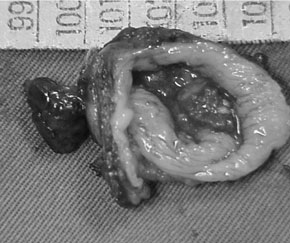

30 dia pós-operatório. O exame histopatológico

confirmou divertículo de pulsão, caracterizado

por herniação da mucosa e submucosa

esofagiana. Ausência das camadas musculares

próprias da parede e presença de esofagite

inespecífica severa, crônica e aguda com hiperplasia

epitelial no interior do divertículo.

|

|

| Figura 3 - Peça cirúrgica |